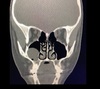

Sinusitis izq Mucocele derecho (es convexo)